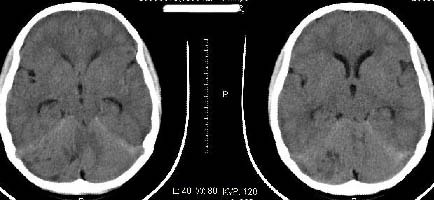

以下是引用子期在2009-6-10 21:34:00的发言:[br]髓母细胞瘤一般位于中线附近和小脑蚓部,该病灶位于右侧小脑半球,倾向于毛细胞型星形细胞瘤,当然也不能完全排除髓母细胞瘤。

以下是引用随光逐影在2009-6-10 22:26:00的发言:[br]考虑右侧小脑胶质瘤,髓母细胞瘤待排。

以下是引用影象小泰斗在2009-6-10 22:14:00的发言:[br]年龄及影像表现军符合小脑星形细胞瘤表现![br]期待病理结果!